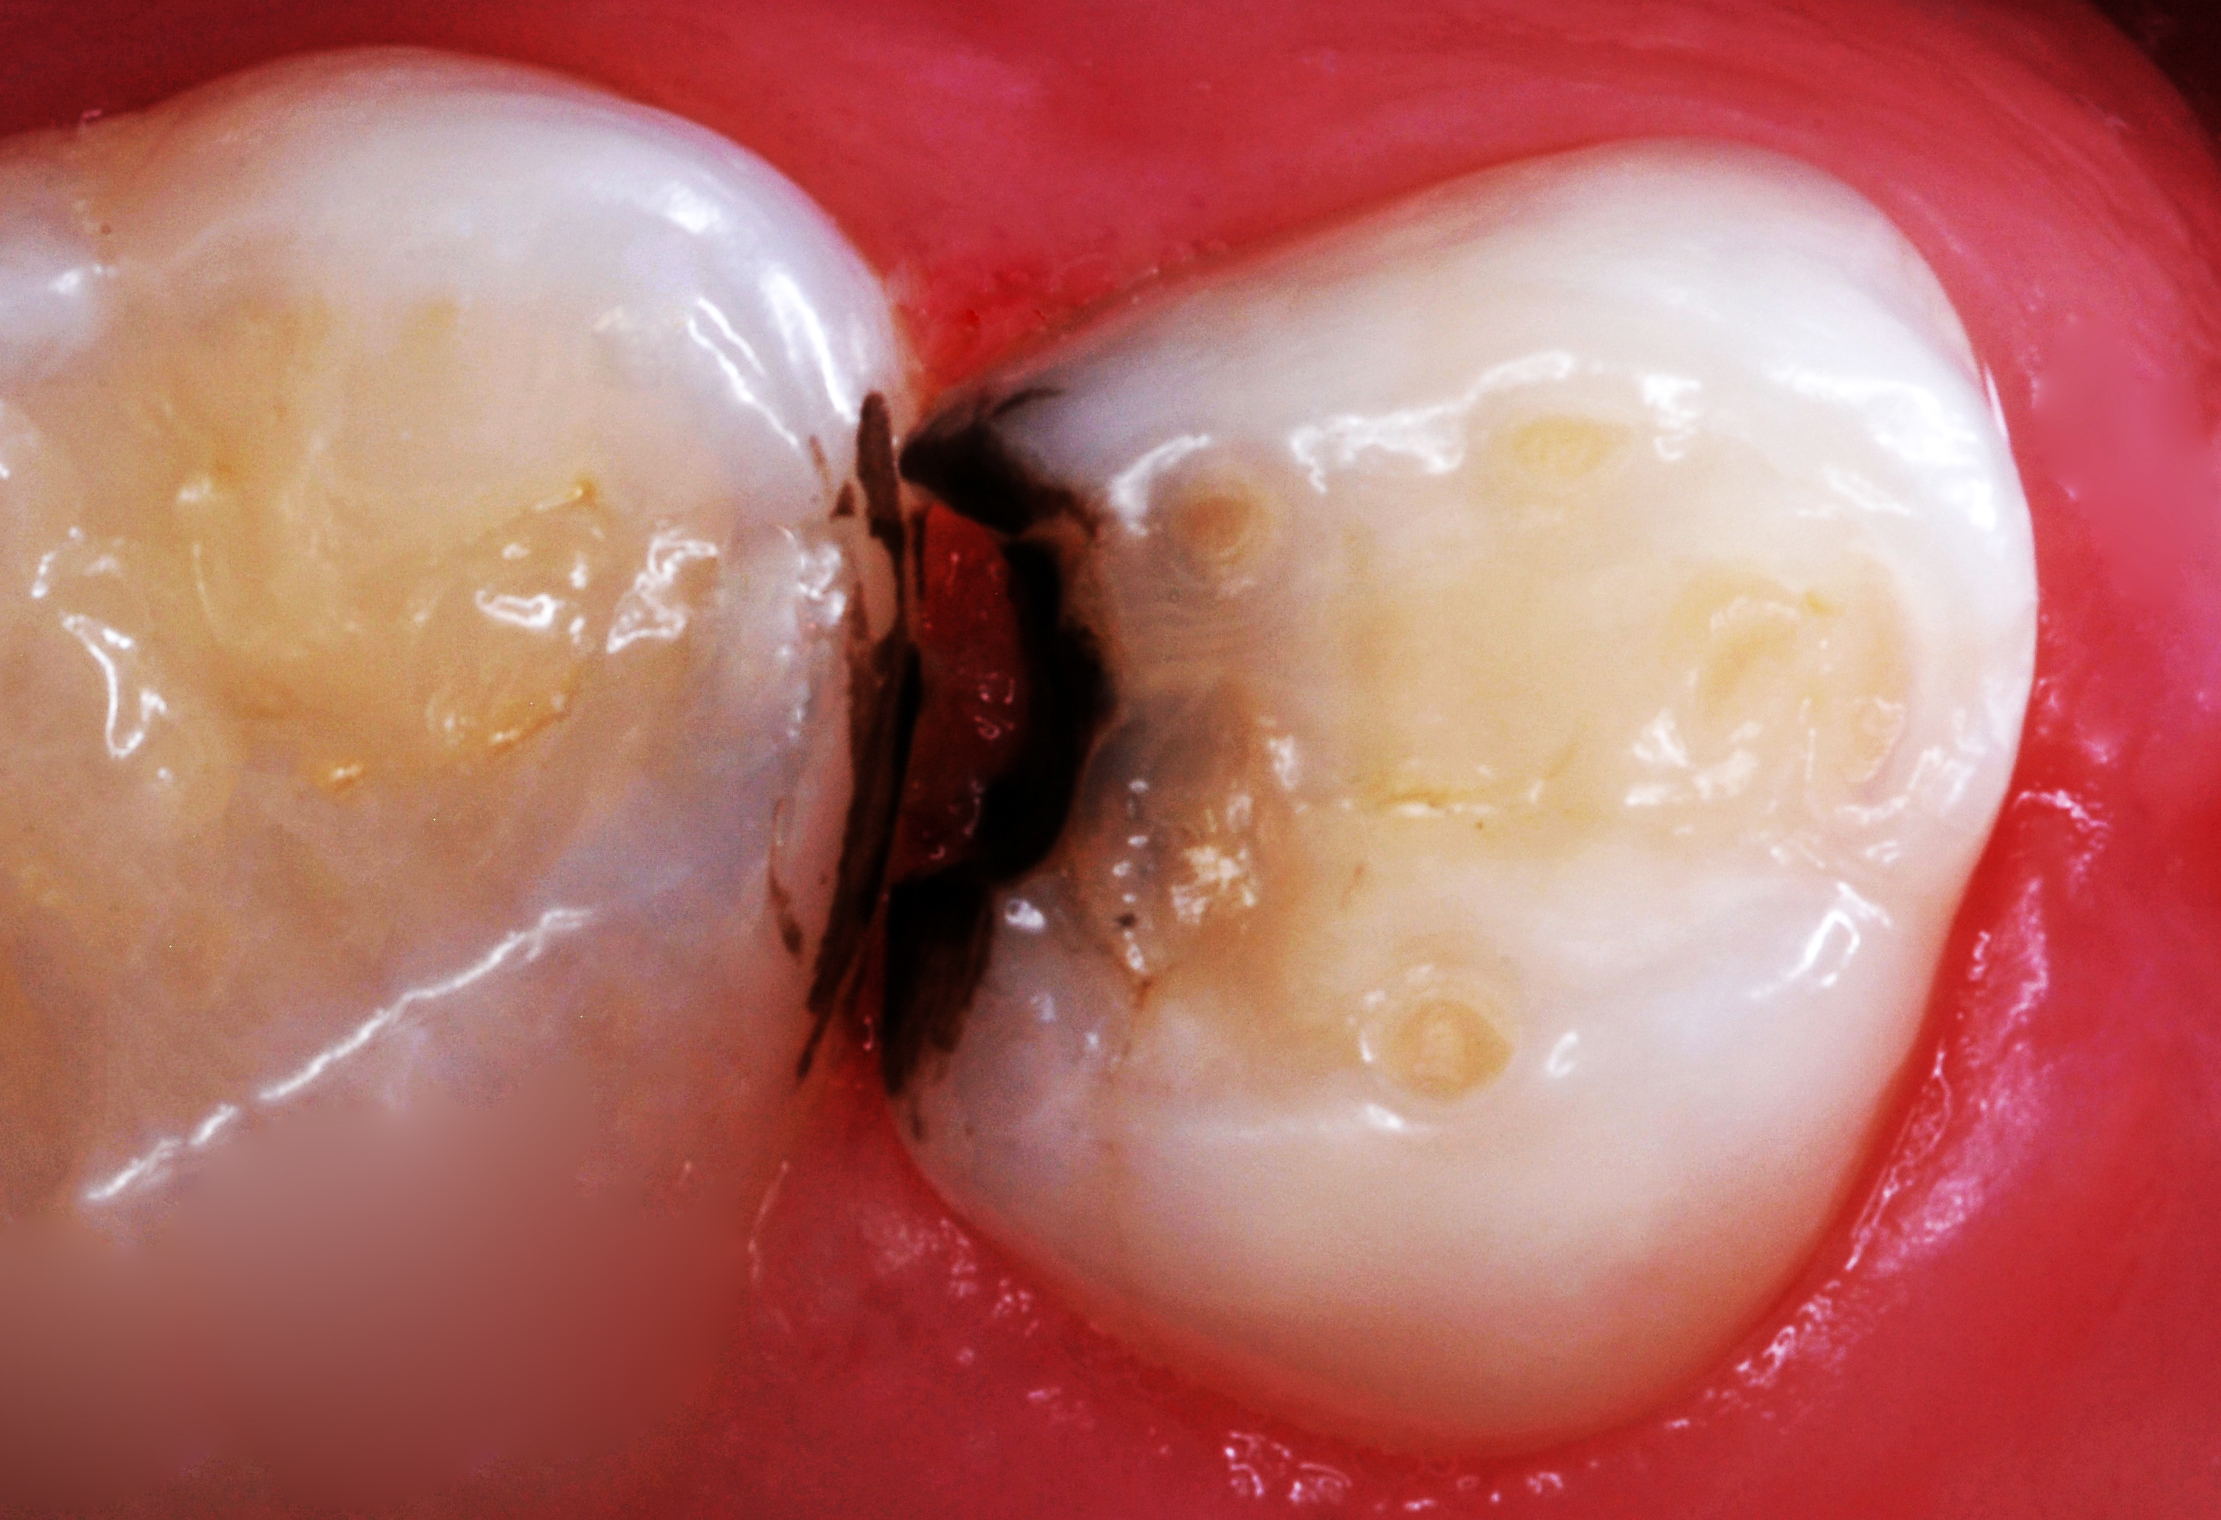

(26.) Silver modified atraumatic restorative technique (SMART) caries control treatment demonstrated on extracted carious primary molar.

Figure 26

(27.) Silver modified atraumatic restorative technique (SMART) caries control treatment demonstrated on extracted carious primary molar.

Figure 27

(28.) Silver modified atraumatic restorative technique (SMART) caries control treatment demonstrated on extracted carious primary molar.

Figure 28

(29.) Silver modified atraumatic restorative technique (SMART) caries control treatment demonstrated on extracted carious primary molar.

Figure 29

30.) Silver modified atraumatic restorative technique (SMART) caries control treatment demonstrated on extracted carious primary molar.

Figure 30

(31.) Silver modified atraumatic restorative technique (SMART) caries control treatment demonstrated on extracted carious primary molar.

Figure 31

(32.) Silver modified atraumatic restorative technique (SMART) caries control treatment demonstrated on extracted carious primary molar.

Figure 32